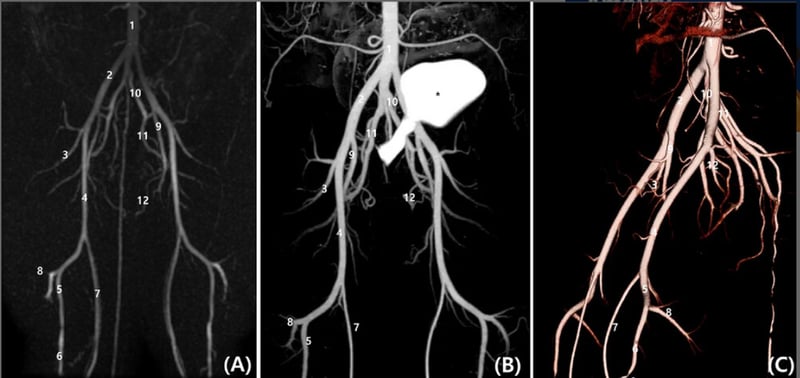

- Vascular

Vascular